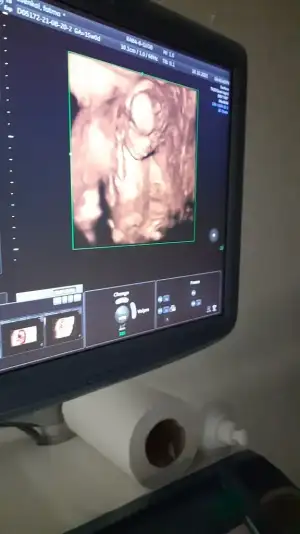

Ogluslar çoğalıyor. Sağlıkla, vaktinde gelsinler inşallah. Renkli ultrason çok güzel birsey bebegi cok net görmemizi sağlıyor.

Ya ne güzel yatmış poz vermiş maşallah

evet ya sürpriz oldu bize de böyle görmek, arkadaşımla aramızda 1 gün var birlikte gidiyoruz ailecek kontrollere